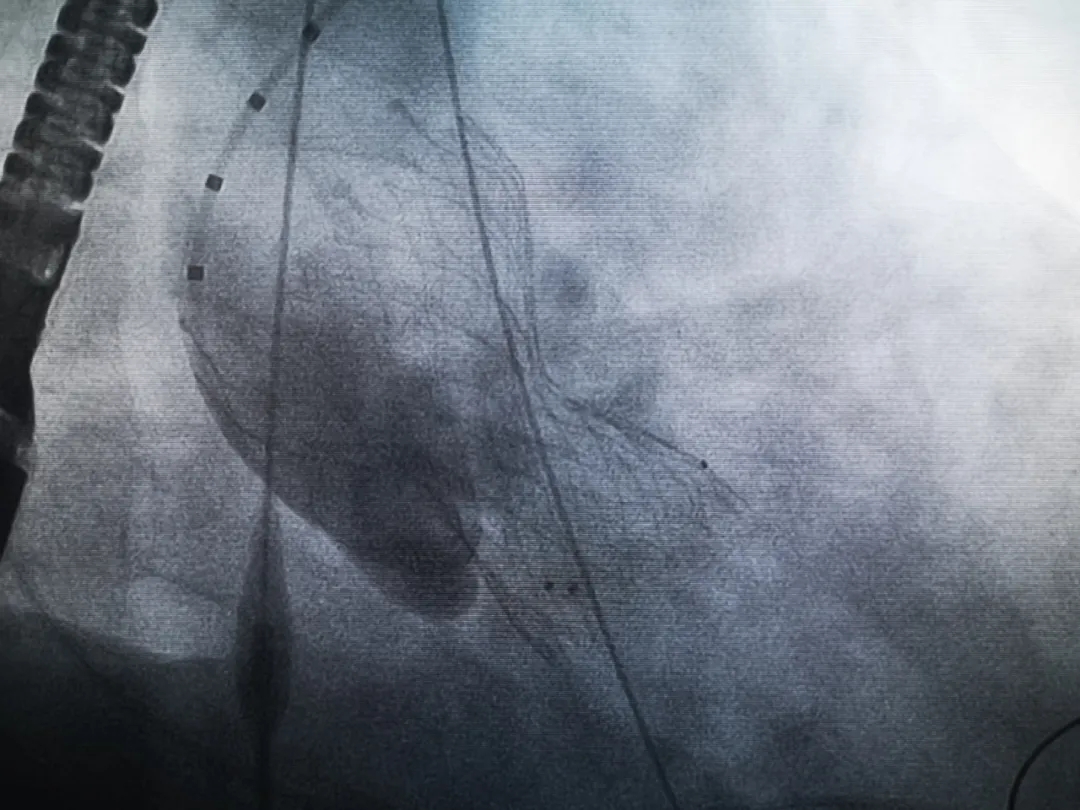

王子的手術(shù)被安排在周五。術(shù)前一天,TAVR團(tuán)隊(duì)再次碰頭討論,從麻醉中血壓控制、球囊擴(kuò)張、瓣膜釋放,到各種可能突發(fā)狀況的應(yīng)對(duì),都提前制定了方案。尤其是瓣膜鈣化極為嚴(yán)重,對(duì)于擴(kuò)張球囊型號(hào)的選擇、擴(kuò)張的力度以及瓣膜植入后瓣周漏的發(fā)生預(yù)測(cè),都具有很大挑戰(zhàn)。然而,如果沒有這些挑戰(zhàn),他又何必選擇我們呢!

手術(shù)過(guò)程緊張而有序,心臟沒有停跳,也沒有太大的血壓波動(dòng);球囊擴(kuò)張的恰到好處,瓣膜釋放之后超聲醫(yī)生的評(píng)估是至關(guān)重要的,因?yàn)槲覀兲崆熬蜏?zhǔn)備了后擴(kuò)張,也準(zhǔn)備了瓣中瓣,甚至還準(zhǔn)備了瓣周漏封堵。所幸的是,超聲診療中心劉夢(mèng)梅醫(yī)生說(shuō):沒有返流、沒有瓣周漏,瓣膜形態(tài)良好,跨瓣壓差約17mmHg(相較于術(shù)前的87mmHg還是可以接受的)。瓣膜置入的成功并不是慶祝的時(shí)候,從戰(zhàn)場(chǎng)撤退仍然需要謹(jǐn)慎。由于王子特別胖,腹股溝區(qū)脂肪尤為肥厚,在股動(dòng)脈插管拔除、確認(rèn)搏動(dòng)正常之后,便逐層縫合。同時(shí)為了美觀、縫合之后不至于鼓個(gè)包出來(lái),我們又仔細(xì)剪除了部分脂肪。術(shù)后次日,王子便可以下床活動(dòng)了。